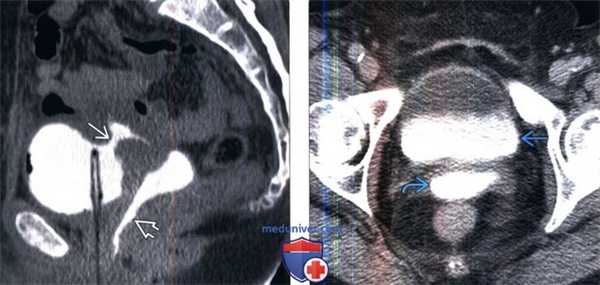

(Слева) КТ-цистография, сагиттальный срез: у пациентки с пузырно-маточным свищом в анамнезе, возникшим после кесарева сечения, определяется свищевой ход между мочевым пузырем, внутри которого находится постоянный катетер, и маткой. Выявлено последующее заполнение влагалища контрастом.

(Справа) КТ с контрастированием в отсроченную фазу: у этой же пациентки в мочевом пузыре и во влагалище определяется контрастируемая моча. В некоторых случаях необходимо тугое заполнение мочевого пузыря или влагалища с прямым введением контраста для обнаружения свища.